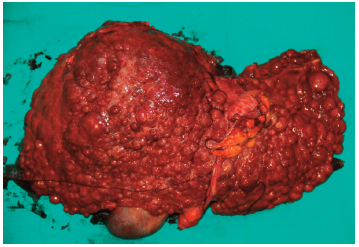

On admission, the patient presented with dyspnea, orthodeoxia, platypnea, cyanosis, and weakness. Transthoracic echocardiography revealed a bicuspid aortic valve and pulmonary arteriovenous fistula, without pulmonary hypertension. Liver computed tomography-angiography demonstrated HCC in the right lobe, associated with splenomegaly and throm-bosis of the right portal vein (Figure 1). Preoperative chest radiography was normal, and the electrocar-diogram showed regular sinus rhythm. On room air in the supine position, venous oxygen pressure was 79 mm Hg with oxygen saturation of 92%. Laboratory findings were as follows: hemoglobin 10.4 g/dL, hematocrit 31.7%, platelet count 45×103/μL, alanine aminotransferase 23 IU/L, aspartate aminotransferase 105 IU/L, gamma-glutamyl transferase 107 IU/L, total bilirubin 1.5 mg/dL, direct bilirubin 1.3 mg/dL, albumin 2.6 g/dL, and international normalized ratio 1.4. Other parameters were within normal limits. The patient’s Child-Pugh-Turcotte score was B, and her Model for End-Stage Liver Disease score was 6. According to the American Society of Anesthe-siologists physical status classification, she was class III, and the Mallampati score was II.

Figure 1. Liver Computed Tomography-Angiography of Patient, Showing Multiple Nodules in the Liver Parenchyma